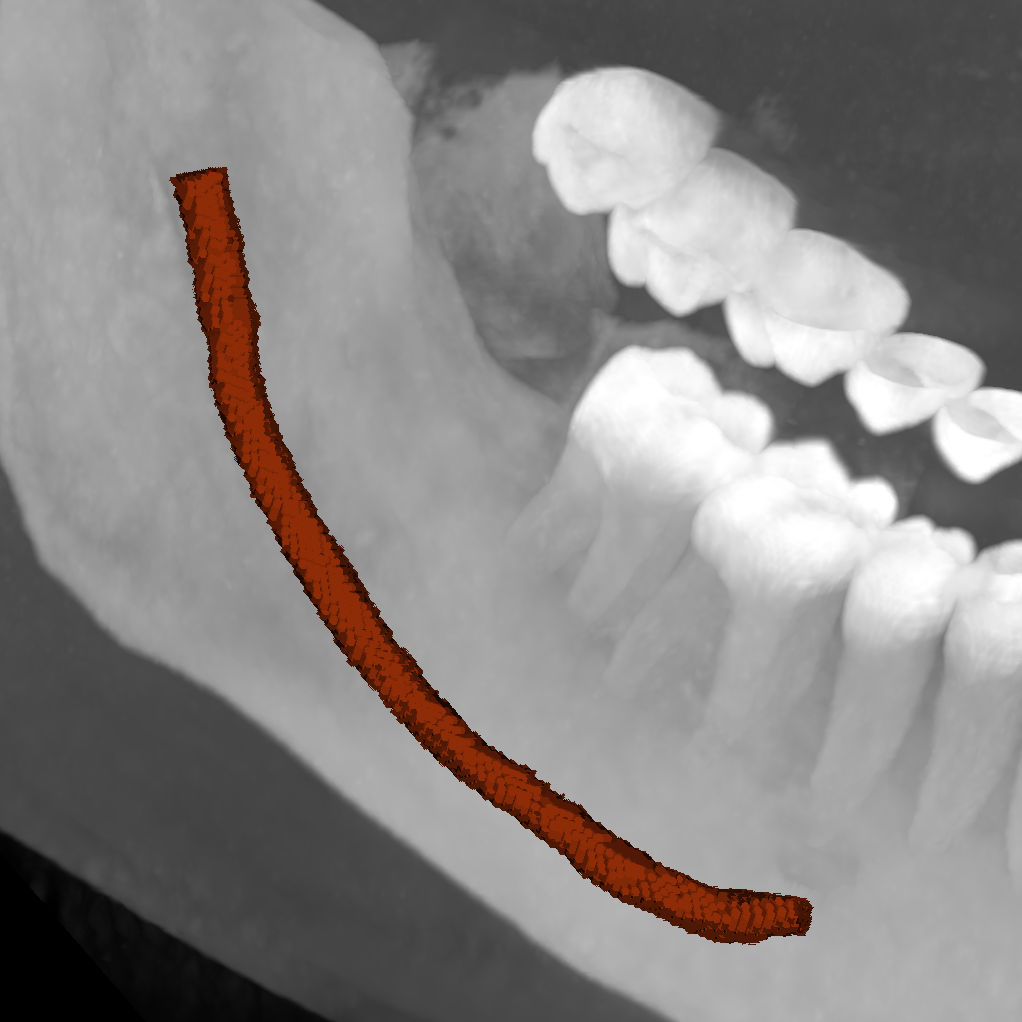

| ToothFairy[6, 5] | 3D | binary | 138 | Inferior Alveolar Canal |

We employ five public datasets featuring thin structures for validating the proposed Skeleton Recall Loss. The datasets span natural as well as medical images, covering a range of segmentation challenges, including both binary and multi-class segmentation problems in 2D as well as 3D contexts. An overview of the datasets can be found in Tab. 1. Among the three 2D datasets used in this study, the Digital Retinal Images for Vessel Extraction (DRIVE) dataset [32] was employed, focusing on retinal vessel segmentation. Additionally, structural inspection images designed for concrete crack segmentation (Cracks) [36] and aerial images of Massachusetts for road segmentation (Roads) [21] were included, highlighting the diversity of thin structures in natural and constructed environments. In the 3D domain, we incorporated two cutting-edge medical image segmentation challenge datasets. One of them was ToothFairy111https://toothfairy.grand-challenge.org/, which was a segmentation challenge on 3D Cone-Beam CTs [6, 5] featuring the inferior alveolar canal as the target structure. Additionally, the TopCoW222https://topcow23.grand-challenge.org/ dataset for topology-aware 3D segmentation of vessels in the Circle of Willis for CTA and MRA data [40] was utilized, encompassing binary as well as multi-class segmentation on 13 different subtypes of vessels. This diverse set of datasets enables a comprehensive evaluation of the proposed Skeleton Recall Loss, demonstrating generalizability of the method to a wide range of thin structure segmentation challenges in both 2D and 3D contexts.